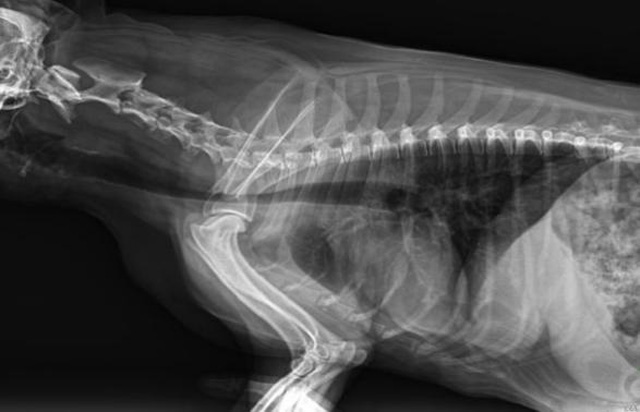

從臨床角度出發,大力發展動態DR,以精準的診斷為小動物保駕護航。寵物DR升級使用雙焦點球管,大尺寸平板探測器,超高頻逆變高壓發生器。醫用纖維板台麵,防止寵物劃傷。寵物DR整機小巧實用,骨略結構和器官位置,分類詳細,運算更快,讓拍攝條件更科學,有助於提高診斷的準確性和效率。安裝移動非常方便。低輸入電流設計,220伏常規電壓。多品種動物程序設定,滿足各個臨床需求。成像效果顯著,寵物不能言語表達,導致誤診率居高不下。寵物診療均以經驗診斷為主的方式,確保最小化輻射降低對醫生及動物的影響。以滿足精細化的寵物醫療需求,成為診斷寵物內外科疾病的必備工具。使醫院更有競爭力,為醫院創收增光添彩。

寵物DR的操作流程是什麽呢?第一步首先插上整機電源,然後按下主機電源。打開高壓發生器的電源,工作站主機電源。等待主機軟件的自動啟動。通過軟件登記檢查的寵物信息,選擇寵物檢查拍攝部位。調節限速器拍攝區域。關閉鉛房門,點擊開始拍攝按鈕。拍攝完成調整圖像並且輸出。